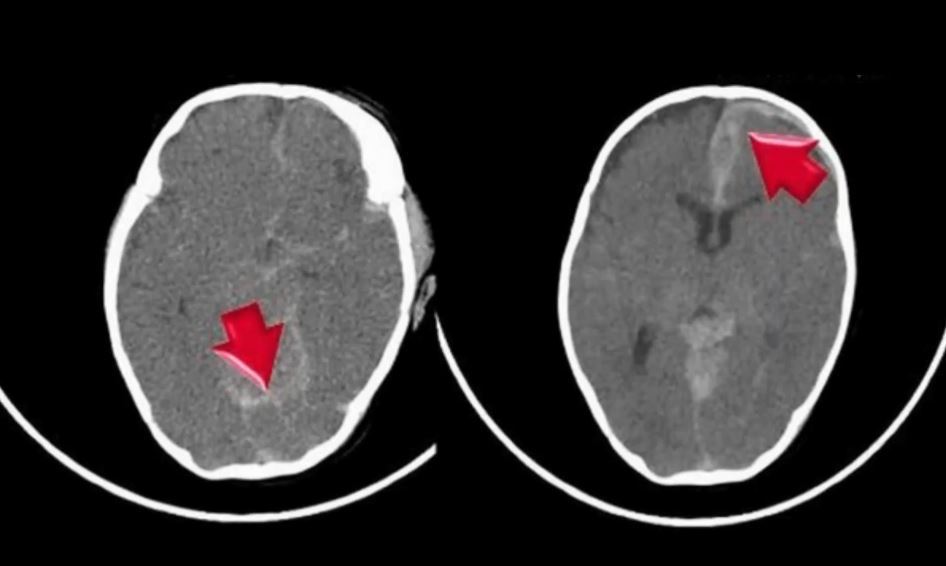

更令人不捨的是,男嬰生前竟遭父母虐待,劉姓夫妻疑似因為小孩哭鬧,曾經拿鞋子丟擲嬰兒,並把男嬰抱起大力搖晃、毆打頭部。2016年12月,父母聲稱男嬰嗆奶轉送到台中的醫院,12天後宣告不治,醫院方面發現男嬰頭部有「顱內出血」等舊傷,馬上經台中家暴防治中心通報苗栗縣社會處,但當時先以嗆奶製死結案。

▼(圖/東森新聞)

直到2017年1月收到醫院診斷證明,社會局正式以兒虐案提告劉姓夫妻,這時男嬰遺體早已火化3個月。苗栗縣社會處副處長張國棟:「報告死亡(原因)還是以溢奶致死,但是他裡面有包含其他陳舊性的傷害,是有些疑慮的,因為到底孩子是溢奶的狀況死亡呢?還是他有其他問題?所以我們在去年4月時候提出一個獨立的告訴,希望檢調單位幫我們釐清這個孩子真正死亡的原因。」